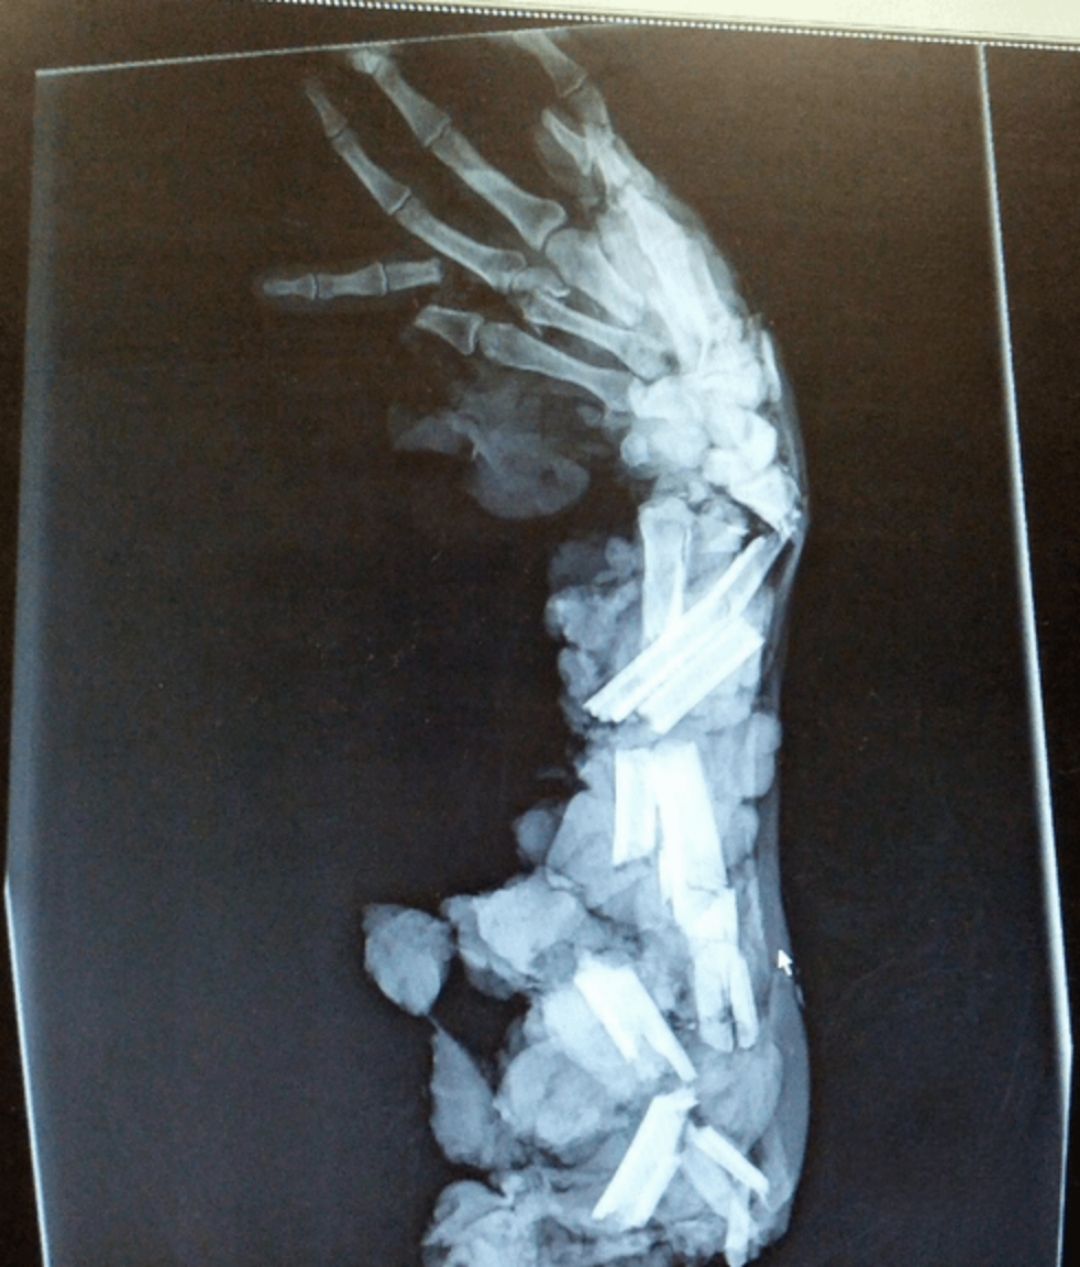

Siis mää sain Lappalaisen röntgen kuvan haltuuni sen iskun jälkeen.

On kyllä pieni ihme, että ura ei ole ohi.